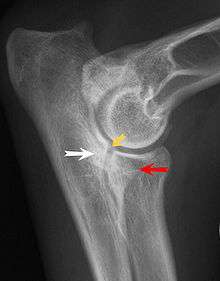

Most primary lesions are related to osteochondrosis, which is a disease of the joint cartilage and specifically Osteochondritis dissecans (OCD or OD), the separation of a flap of cartilage on the joint surface. Other common causes of elbow dysplasia included ununited anconeal process (UAP) and fragmented or ununited medial coronoid process (FCP or FMCP).[1]

The most common cause is osteochondrosis, which is a disease of the joint cartilage, and specifically Osteochondritis dissecans (OCD or OD), the separation of a flap of cartilage from the joint surface[1] as a result of avascular necrosis, which in turn arises from failed blood flow in the subchondral bone.[3] Other common causes of elbow dysplasia included ununited anconeal process (UAP) and fractured or ununited medial coronoid process (FCP or FMCP).[1]

In OCD, the normal change of cartilage to bone in the development of the joint fails or is delayed. The cartilage continues to grow and may split or become necrotic. The cause is uncertain, but possibly includes genetics, trauma, and nutrition (including excessive calcium and decreased Vitamin C intake).[4] OCD lesions are found in the elbow at the medial epicondyle of the humerus. Specific conditions related to OCD include fragmentation of the medial coronoid process of the ulna (FMCP) and an ununited anconeal process of the ulna (UAP). All types of OCD of the elbow are most typically found in large breed dogs, with symptoms starting between the ages of 4 to 8 months.[4] Males are affected twice as often as females. The disease often affects both elbows (30 to 70 percent of the time), and symptoms include intermittent lameness, joint swelling, and external rotation and abduction of the paw.[5] Osteoarthritis will develop later in most cases.

UAP is caused by a separation from the ulna of the ossification center of the anconeal process.[6] FMCP is caused by a failure of the coronoid process to unite with the ulna. OCD of the medial epicondyle of the humerus is caused by disturbed endochondral fusion of the epiphysis of the medial epicondyle with the distal end of the humerus, which may in turn be caused by avulsion of the epiphysis.[7]

Diagnosis is through x-rays, arthroscopy or CT (computed tomography). In cases with significant lameness, surgery is the best option, especially with UAP. However, conservative treatment is often enough for cases of FMCP and OCD of the medial humeral epicondyle. The dogs are exercised regularly and given pain medication, and between the ages of 12 to 18 months the lameness will often improve or disappear.[4] Control of body weight is important in all cases of elbow dysplasia, and prevention of quick growth spurts in puppies may help to prevent the disease.